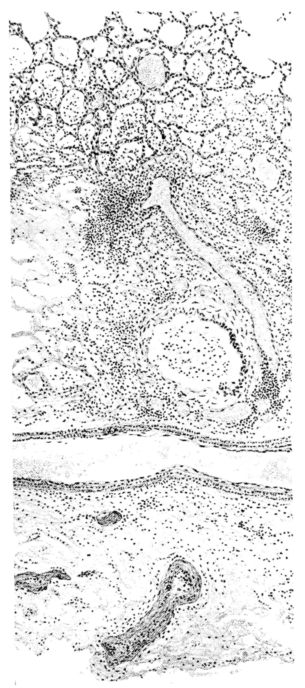

No matter what the portion of the lung from which the sections are derived, the fundamental changes found are the same. The subpleural sheets are spread wide apart, now by empty spaces, now by coagulated fluid. The process extends from the surface through the interlobular septa (Fig. XX), and is accentuated where the connective tissue is more prominent around vessels and bronchi. The nature of the infiltrate in the subpleural and interstitial tissues becomes more evident in the alveoli, which likewise are filled. The material varies somewhat in appearance, probably dependent upon its proteid content. Not infrequently the alveoli contain a homogeneous, pink-staining mass, which resembles the colloid of the thyroid gland. Again, it may be simply a coarse granular precipitate (Fig. XXIII), and in still other instances, small sticks and strands form the bulk of the alveolar content (47, 92, 140, 156). This subpleural, interstitial, perivascular, peribronchial, and alveolar edema, which is a term applicable to this collection of fluid, is very prominent, and although its intensity varies in different portions of the lung; and although it may be replaced in some areas by other types of exudate, unquestionably, this is the dominating expression of the inflammatory process in the early stage of the disease.

As might be expected from the gross appearance, the alveoli vary in size. At times slightly collapsed and at other times overdistended, their lumina are still the seat of the inflammatory exudate, although the mechanical change may allow of some variation in the appearance of their walls. As a rule, however, the alveolar wall is prominent and owes its conspicuousness to the tortuous, engorged vessels within. These vessels contain red blood cells almost exclusively, and on account of the partial, occasionally complete, loss of the lining epithelium, the alveolar wall appears as a huge, dilated arteriole (101) separating the lakes of coagulated material in the spaces (Fig. XXIII). There are areas, as indicated above, where the alveolar content may be more definitely arranged in the form of beaded or homogeneous strands of different caliber; the smallest resemble delicate threads. They tend to converge toward the alveolar wall like wheat in a sheaf, and often pass through this wall by way of the so-called pores of Cohn; as soon as the body of the neighboring alveolus is reached, they again present a fan-like expansion into innumerable, fine strands (Fig. XXII). Where the exudate is more fibrinous, the alveolar wall is less likely to be distended, its vessels are not so prominent, and their content of red blood cells is definitely decreased. Still this is not the most extreme type of alveolar exudate met with at this stage. Perhaps, the most striking, although not the most frequent, exudate has a superficial resemblance to a huge, red blood clot, and it may be difficult to make out the alveolar walls separating the masses of well preserved red blood cells that fill the alveolar spaces. These areas are indistinguishable from infarcts and may be associated with thrombotic arteritis in near-by pulmonary vessels (47) (Figs. XXIV and XXV). Among the red blood cells an occasional strand of fibrin, a desquamated alveolar epithelial cell, and rarely a polymorphonuclear leucocyte may be encountered. The alveolar wall itself varies in the definition of its outline. When its vessels are greatly distended, when its alveolar epithelium is gone, and when its content consists largely of red blood cells, it is difficult to distinguish from the exudate which it encloses. However, when it is more compressed or when its epithelial lining cells are still more or less intact, it may be seen as a blue-staining strand under the low power of the microscope, for the well preserved nuclei lend it prominence.

21There are, of course, variations in the extent of the serum, the fibrin, and the hemorrhage in the exudate of the alveoli, and while these different types may occur as pure forms, often they are associated. In still other areas and varying in prominence, one finds as characteristic an exudate, not only of serum, strands of fibrin, and red blood cells, but also a diffuse dotting of the exudate with bacteria, singly, in pairs, clumps, and chains (92, 164) (Fig. XXI). This type of reaction is uncommon in pulmonary disease. It resembles more closely a streptococcus cellulitis such as is encountered frequently in the subcutaneous tissues, for example, a woody phlegmon, or a sero-hemorrhagic exudate like the avirile response to a rapidly fatal hemolytic streptococcus serositis. A similar reaction has been reproduced experimentally in animals which have been rendered aplastic with benzol previous to pulmonary insufflation, and it is conceivable that the lack of polymorphonuclear response in the inflammatory exudate may be associated with some such general destruction or temporary suspension of leucocytic formation (160).

A more striking picture, however, even than this aplastic alveolar exudate appears in the terminal bronchioles. In many instances, these are conspicuous on account of their size, for they are dilated to form prominent, often irregular, sacs (Fig. XV). The distention of these terminal bronchioles may be so great that the surrounding alveoli are compressed. What makes them even more conspicuous is their lining, once epithelium, but now a swollen, thick, homogeneously staining material, with complete loss of architecture; the material forms (with hematoxylin and eosin) a red band limiting the lung tissue and sharply demarcating it from the exudate within the bronchioles (48, 92). However, this ribbon of red, often thickened by fibrin deposition, is not always pure, for bacteria thrive in the dead tissue. They occur singly, paired, in chains, and also as circumscribed, dense masses which in size and position, simulate nuclei (162) (Fig. XVI). This same hyalinization of the epithelium, it will be recalled, occurs in the larger bronchi (Fig. V), and there, too, bacteria frequently develop in the dead tissue (Fig. VIII). In the smallest bronchiolar ramifications, acute epithelial necrosis is not infrequently encountered, even when the surrounding lung tissue is relatively normal (Fig. XVI). That the process does not stop with the epithelium, but, as in the larger bronchi, may extend through the entire structure of the bronchioles, is manifest. Even the alveolar walls may be involved and frequently homogeneous pink or red bands, now the phantom of the former viable lung tissue, mark the presence of the old wall of the alveolus (Fig. XVII). Occasionally, some architecture remains in this pink ribbon and then the involvement seems to be primarily in the vessels of the wall. Not all the vessels are involved, and next to a hyaline thrombus in one, there may be fresh blood, usually red blood, in its neighbor. The alveolar epithelium is usually denuded and thus accentuates the intensity of the change.

The acute death which involves the tracheal, bronchial, and bronchiolar epithelium and which may extend beyond the epithelium into the walls of these structures and kill en masse the walls of the alveoli, is a lesion which does not occur in other types of acute pulmonary infection. However, in influenza, as after exposure to pulmonary irritating gases, it is the lesion of characterization (158,159). The effects of this change, of course, where it involves 22the alveolar wall, will vary with the extent of the process; but given an absolutely necrotic wall, as yet unstrengthened by inflammatory reaction, an expected result would be its rupture with respiratory movement. The point of rupture is important, but where so many alveoli are involved, disturbance of continuity will occur, occasionally in such position that the result will be the escape of air into the interstitial tissues.[7] There is ample evidence that this happens. Indeed, among the clinical manifestations of the disease, interstitial emphysema of the lung spreading through the fascial planes to the subcutaneous tissues of neck and thorax is well known; the phenomenon is more frequent and extensive in influenza than in any other disease (8, 17, 52, 143).

Interstitial emphysema is very striking at the post-mortem table. The escaped air appears as beads along the interlobular septa, but on account of their size they are always most conspicuous between the lobes and along the vessels toward the hilum (162) (Fig. XVIII). Histologically, a small bubble of escaped air confined to the interlobular septum compresses the surrounding tissue with almost complete atelectasis of many neighboring alveoli (Fig. XIX).